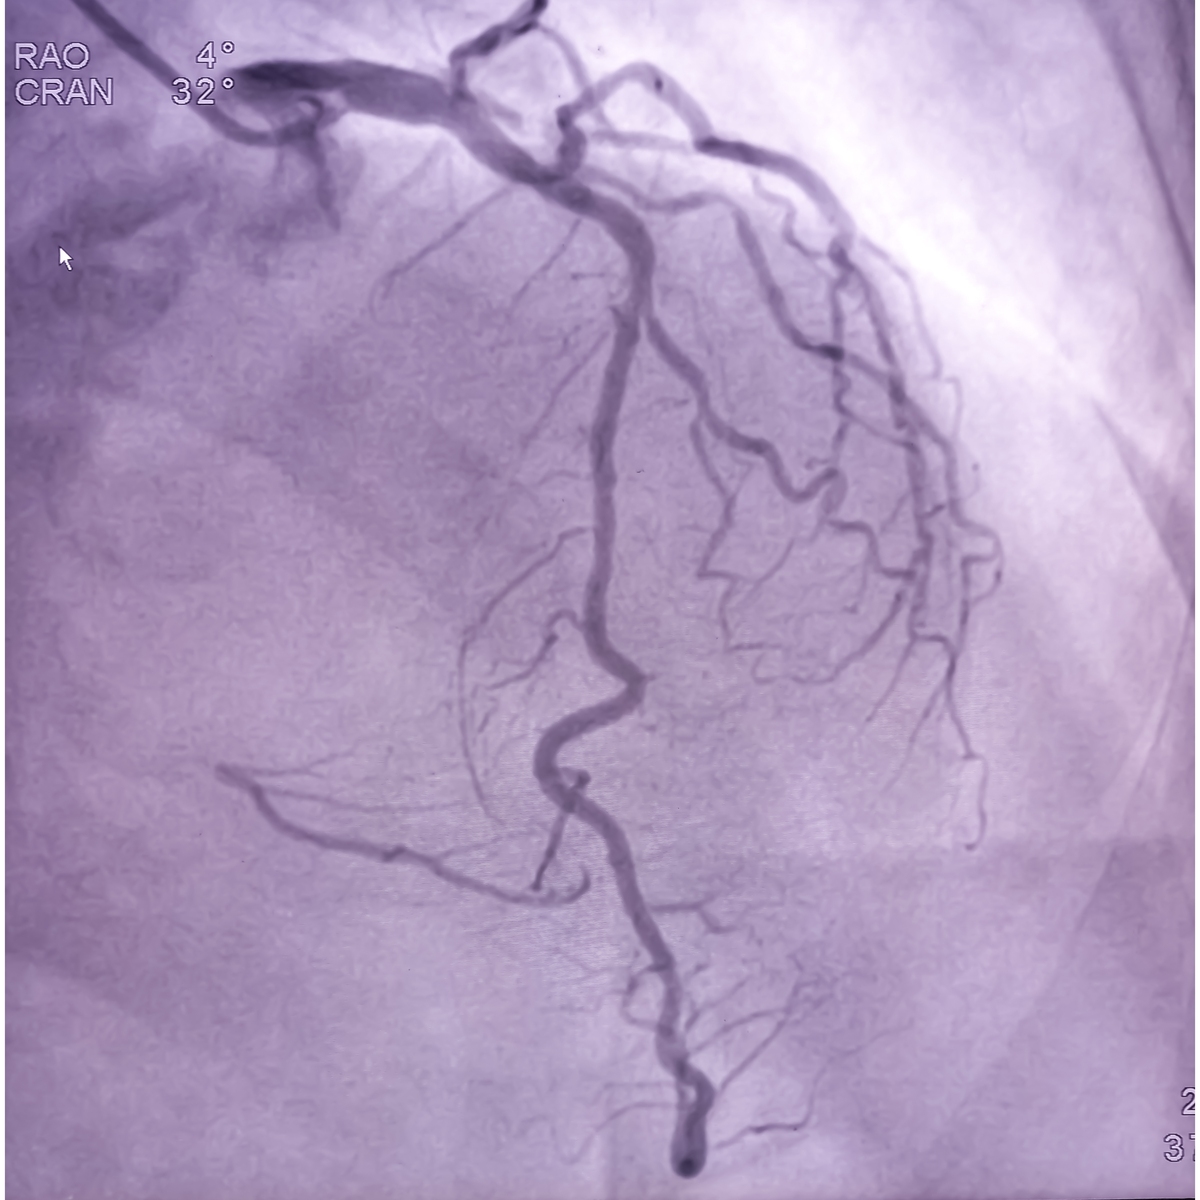

CTA利用X射线和计算机技术创建血管的详细三维图像,可以清晰地显示颈动脉斑块的位置、大小、形态等特征,并判断是否存在破裂。DSA则是一种更具侵入性的检查,通过将造影剂注入血管,实时观察血管内部结构和血流情况,可以更准确地评估斑块破裂的风险。

这两种检查方法各有优缺点,医生会根据患者的具体情况选择合适的检查方案。准确诊断颈动脉斑块破裂对于制定有效的治疗方案至关重要,可以帮助患者降低中风风险,改善预后。